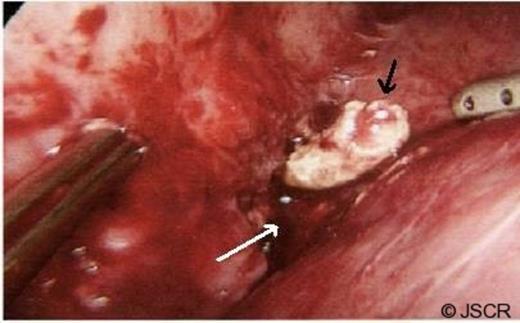

Computed tomography of the abdomen was performed and revealed a 4×3cm structure of low attenuation posterolateral to segment 6 of the liver with surrounding irregular wall and a central 15 mm high density lesion, suggestive of a peritoneal foreign body, possibly a retained appendicolith from previous surgery (Figure 1).

Abdominal CT scan showing a radio-opaque faecolith in the right upper quadrant (arrowed)